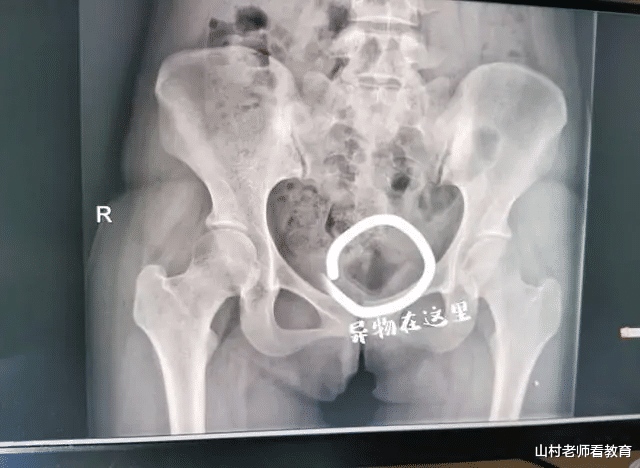

19岁女大学生和男朋友为了寻求刺激 , 将一个长5CM , 直径3CM的异物塞入体内一个月 , 直到异物在体内引发炎症 , 疼痛难忍后才到医院就诊 。

最后在经过医生的检查后 , 确定了小杨体内确实存在一个异物 , 但是由于该异物表面光滑 , 使用普通的器械很难将其取出 , 再加上异物在小杨体内时间较长 , 已经引发了炎症 , 想要取出异物只能使用B超引导 。

经过和小杨商量 , 征得小杨的同意后 , 医生通过B超的探查 , 最终使用手术钳将异物取出 。 这才发现 , 原来这个异物是一个长5CM , 直径3CM的化妆品瓶盖 。